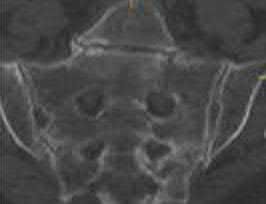

Question 23

A 35-year-old male sustains an APC-III pelvic ring injury following a high-speed motorcycle collision. After initial hemodynamic stabilization, the surgeon elects to perform an open reduction and internal fixation of a widened sacroiliac (SI) joint via an anterior approach. During dissection and plate placement over the sacral ala, which neurological structure is at greatest risk of iatrogenic injury?

Explanation

During the anterior approach to the sacroiliac joint, the L5 nerve root is at significant risk. It courses directly over the sacral ala, typically approximately 2 cm medial to the SI joint, before joining the sacral plexus. Retraction or misplaced drills/screws in this region can easily injure the L5 root, leading to foot drop and sensory deficits.